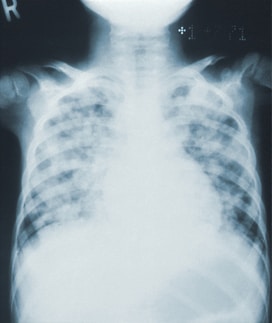

Chest Radiology

Expert reads of complex lung, chest, and mediastinal scans.

Pediatric Radiology

Expert reads of complex diagnostic imaging for children.